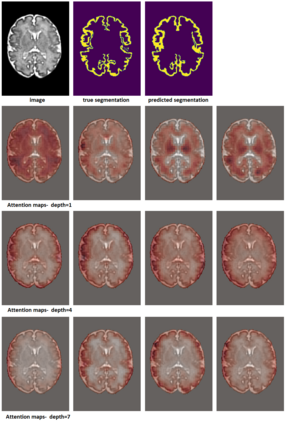

Like other applications in computer vision, medical image segmentation has been most successfully addressed using deep learning models that rely on the convolution operation as their main building block. Convolutions enjoy important properties such as sparse interactions, weight sharing, and translation equivariance. These properties give convolutional neural networks (CNNs) a strong and useful inductive bias for vision tasks. In this work we show that a different method, based entirely on self-attention between neighboring image patches and without any convolution operations, can achieve competitive or better results. Given a 3D image block, our network divides it into $n^3$ 3D patches, where $n=3 \text{ or } 5$ and computes a 1D embedding for each patch. The network predicts the segmentation map for the center patch of the block based on the self-attention between these patch embeddings. We show that the proposed model can achieve segmentation accuracies that are better than the state of the art CNNs on three datasets. We also propose methods for pre-training this model on large corpora of unlabeled images. Our experiments show that with pre-training the advantage of our proposed network over CNNs can be significant when labeled training data is small.